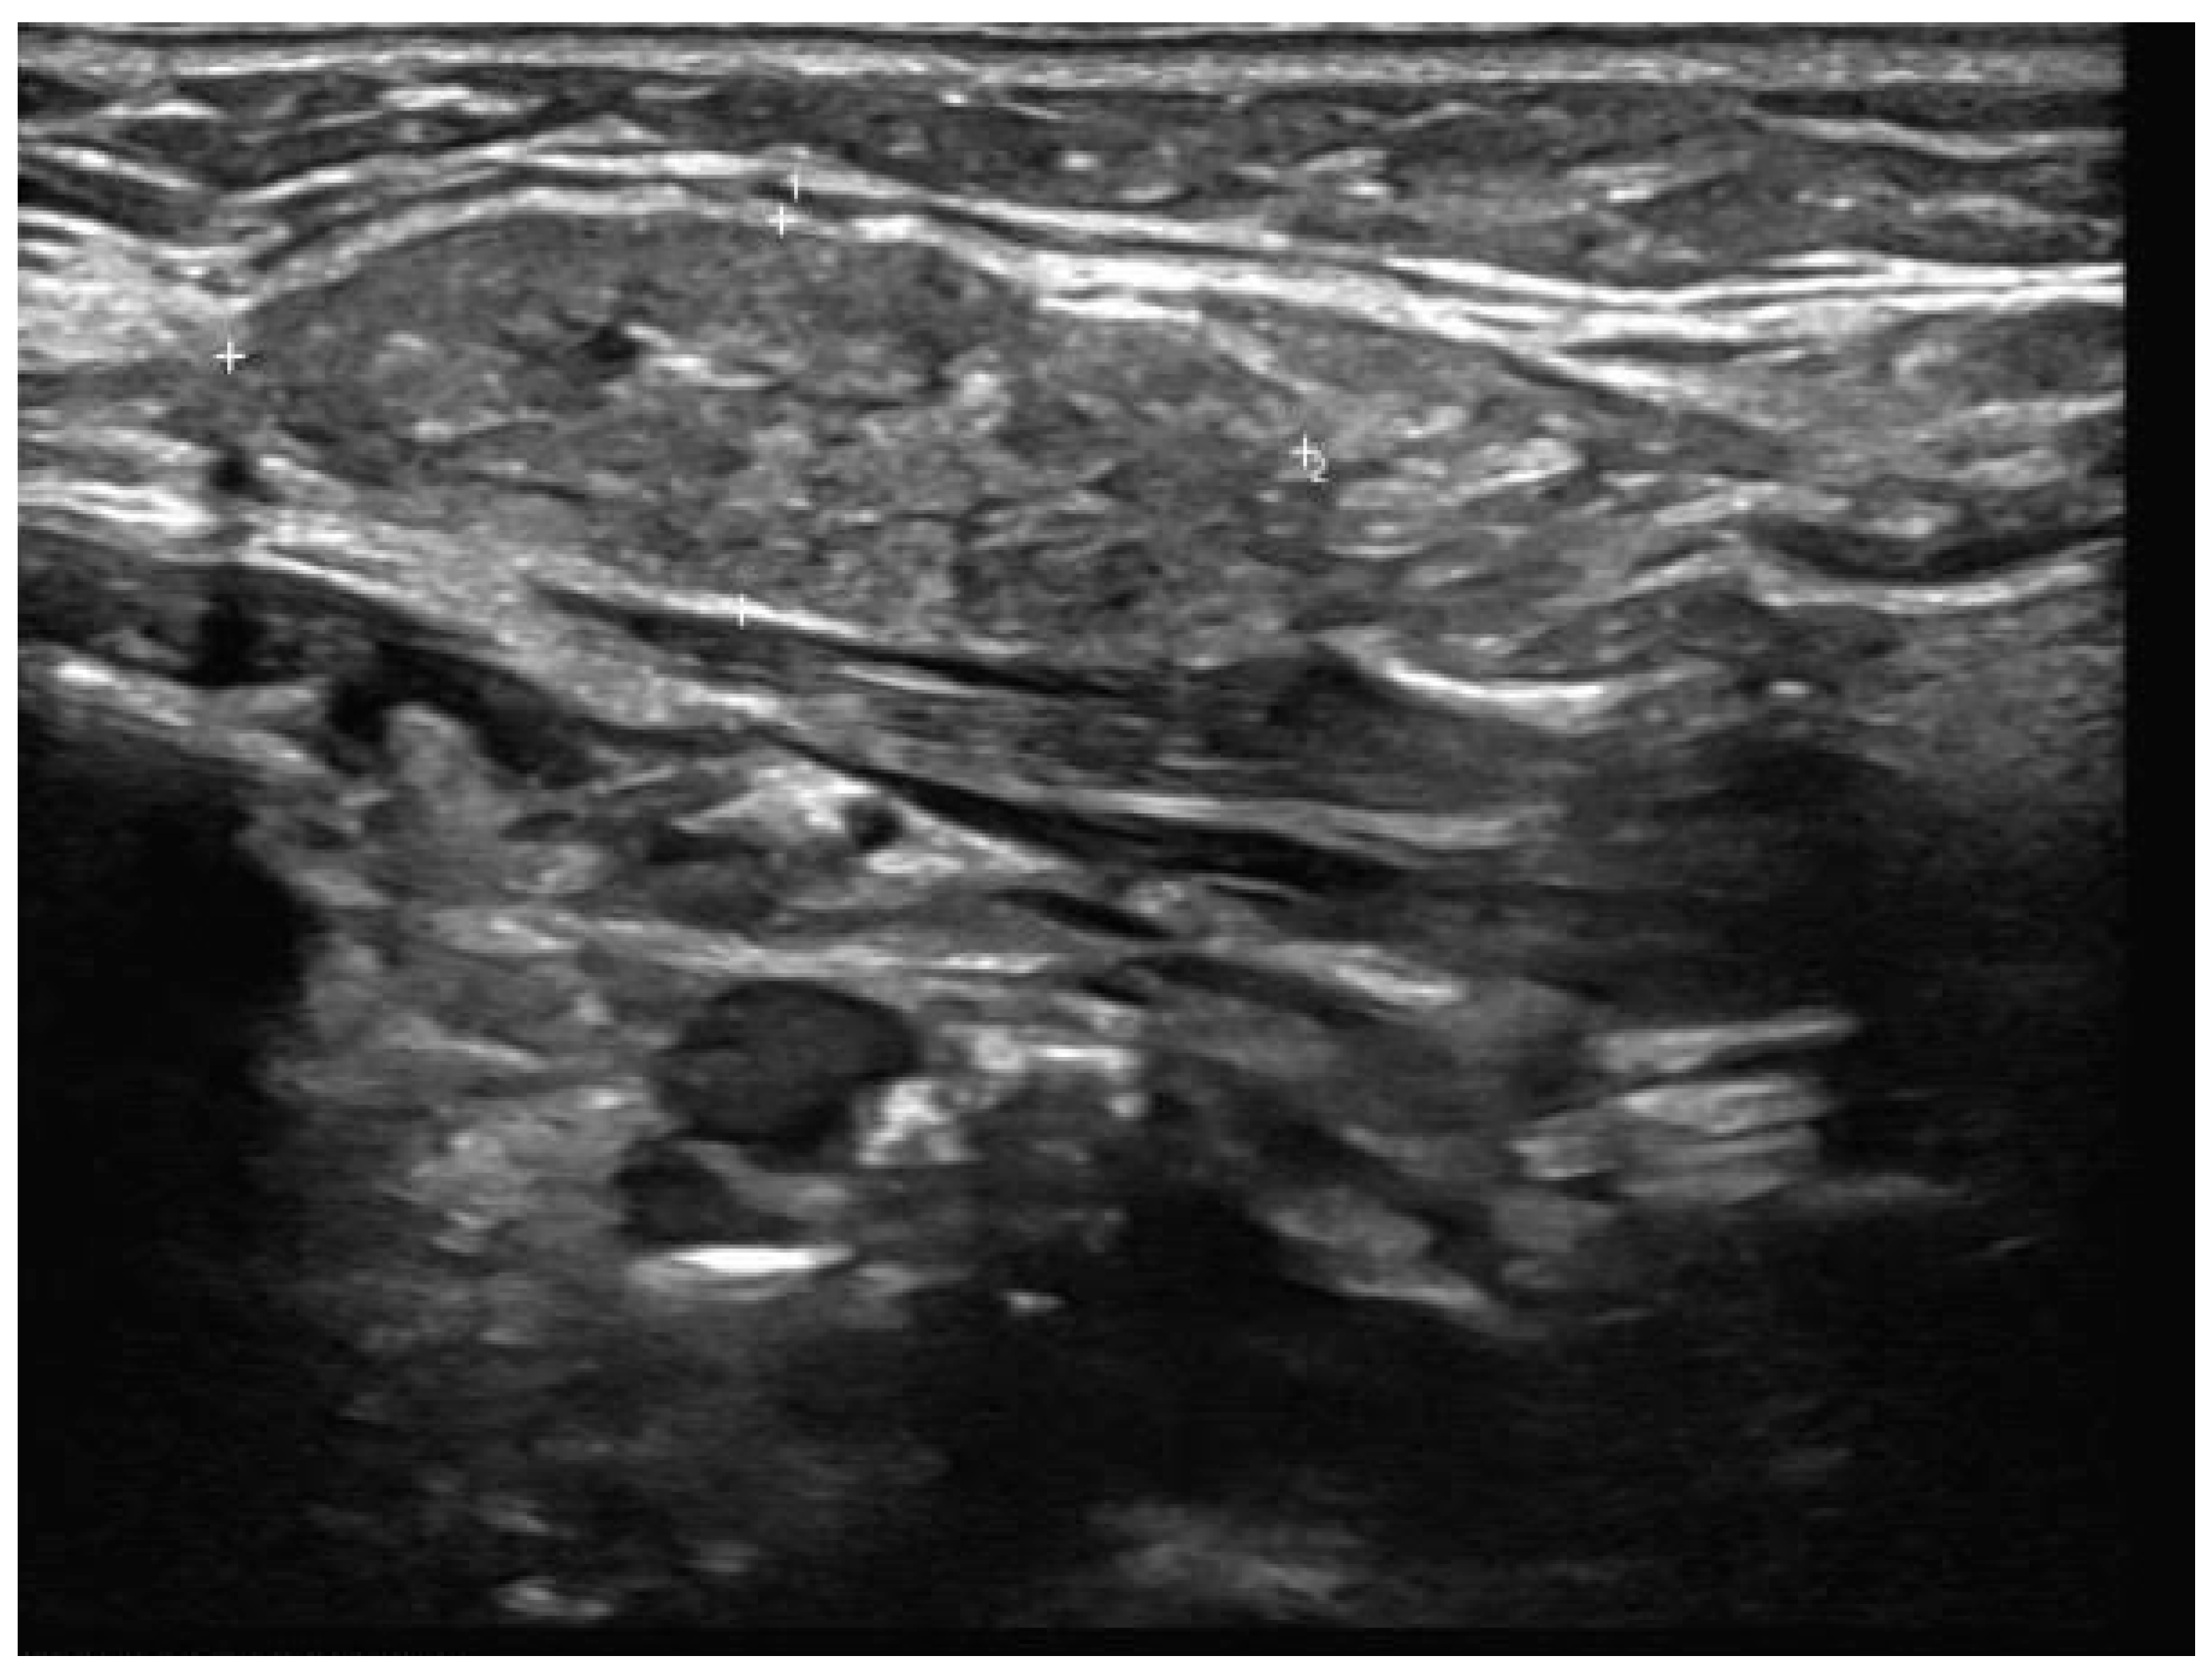

- Well-demarcated geographical area of low echogenicity with increased vascularity;

- Mild focal intrinsic duct dilatation within the SMG;

- No suggestion of a neoplasm or space-occupying lesion.